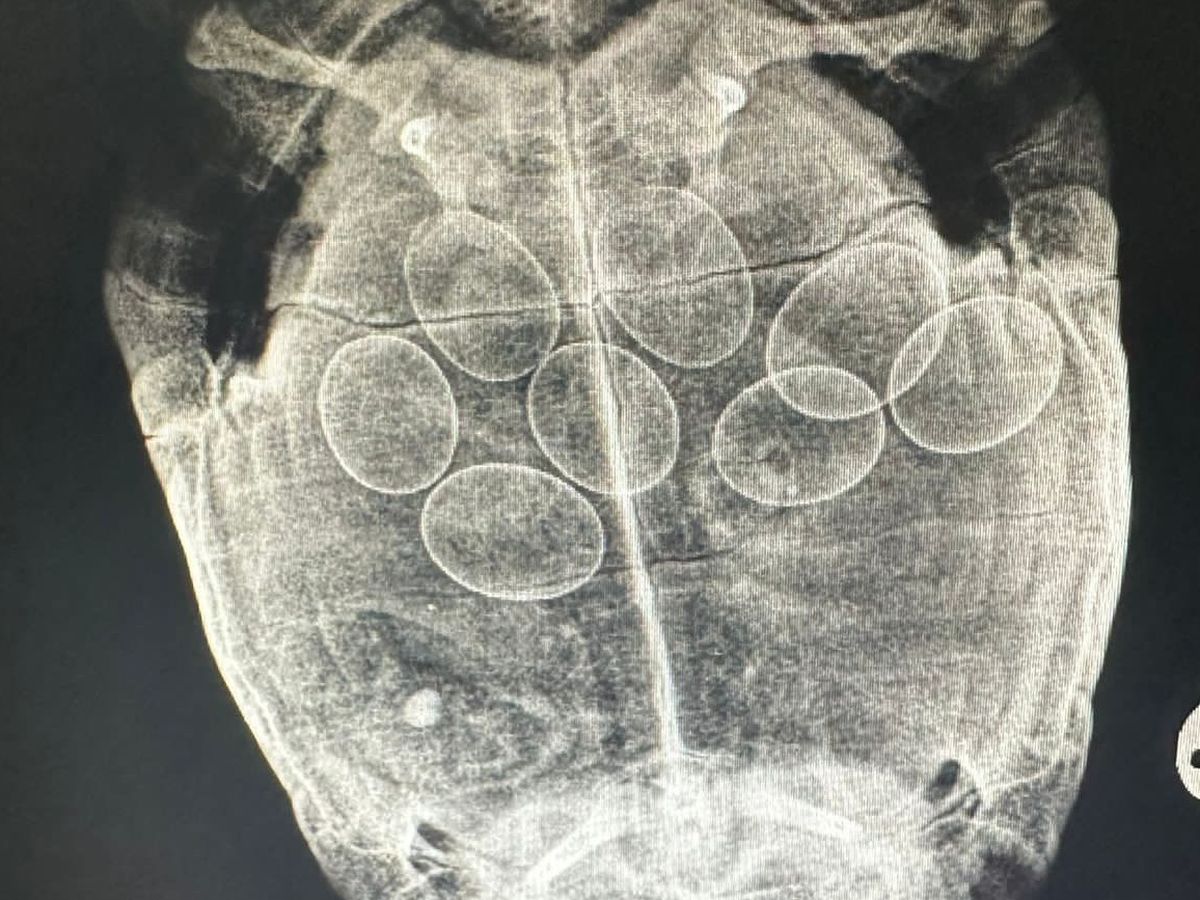

Shelly is our much-loved school tortoise. She had been unwell for a few days so we took her to the vet. After an examination and an x-ray, we found out Shelly has 8 eggs inside of her. After lots of medication and a few days at the vets, she managed to lay all but one egg. She has come home with her medication and is going to have to go back to the vets next week for an operation to remove the final egg. This is going to be a very expensive process and any donations towards the cost would be greatly appreciated.